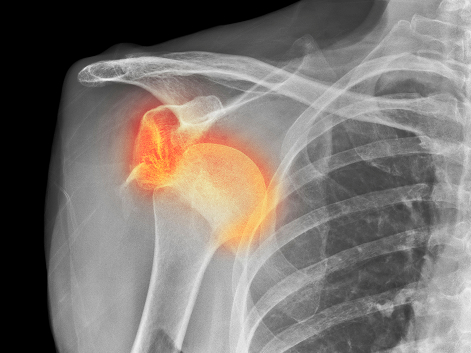

석회화건염은 어깨에 연결된 인대에 석회(돌)가 침착 되어 통증을 유발하는 질환입니다.

칼슘이 침착 되어 결정이 만들어져 극심한 통증을 호소하게 되는데, 환자의 상태에 따라서 석회가 생겼다가 저절로 없어지기도 하지만, 극심한 통증으로 응급실을 찾는 경우도 많습니다.